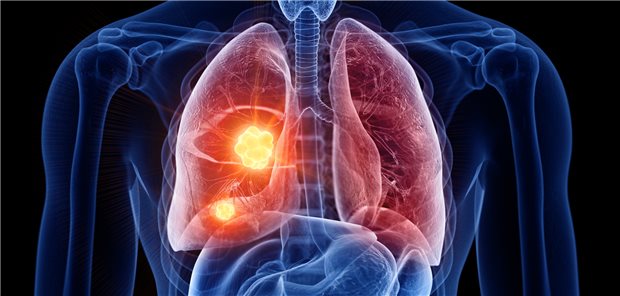

Eine 22-Jährige erlitt beidseitige, multifokale, periphere Lungenembolien. Die Beinvenen sind frei. Ursache war eine mechanische Kompression der rechten Vena subclavia, die Thromboembolien hervorrief. Eine Kasuistik.

Menschen mit NSCLC im Stadium IV, die mit einer Atezolizumab-haltigen Chemoimmuntherapie behandelt werden, haben bessere Überlebensaussichten – niedriggradige immunbezogene Nebenwirkungen vorausgesetzt.

Bei idiopathischer Lungenfibrose ist die Zahl der seneszenten Zellen in der Lunge deutlich erhöht. Sie therapeutisch zu beeinflussen, könnte zur „Verjüngung“ der erkrankten Lunge beitragen.